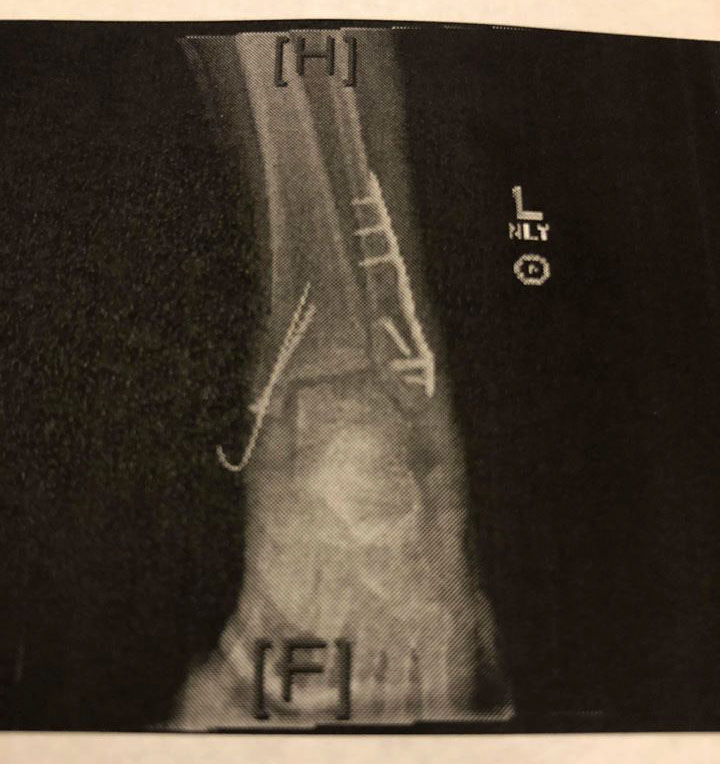

Broken-Ankle-3.jpg My Broken Ankle X-Ray

Now, I am at my daughter’s house in Gilbert, Arizona. My RV is sitting in storage with a third melted stabilizer motor and I am recovering from surgery to install plates and screws and pins in the 3 broken bones in my left ankle.